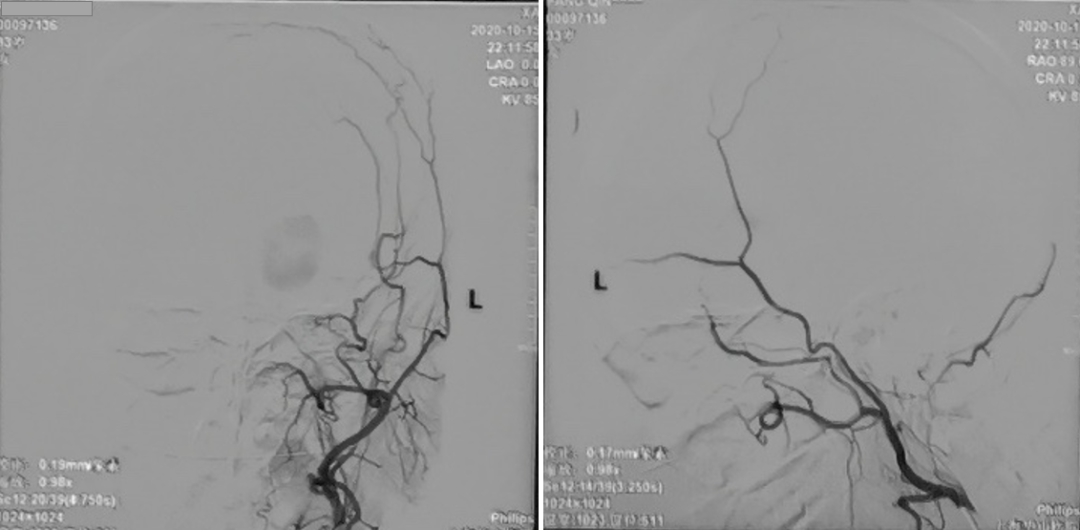

术中电生理未见明显异常,因此未进行进一步血流重建处理。